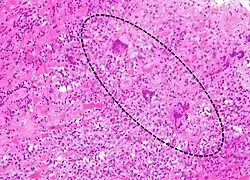

A microscope image of myocarditis at autopsy in a person with acute onset of heart failure. The black dots are primarily lymphocytes infiltrating the myocardium. | |

Most forms of myocarditis involve the infiltration of heart tissues by one or two types of pro-inflammatory blood cells, lymphocytes and macrophages plus two respective descendants of these cells, NK cells and macrophages. Eosinophilic myocarditis is a subtype of myocarditis in which cardiac tissue is infiltrated by another type of pro-inflammatory blood cell, the eosinophil. Eosinophilic myocarditis is further distinguished from non-eosinophilic myocarditis by having a different set of causes and recommended treatments.[36][20]

The gold standard is the biopsy of the myocardium, in general done in the setting of angiography. A small tissue sample of the endocardium and myocardium is taken and investigated. The cause of the myocarditis can be only identified by a biopsy. Endomyocardial biopsy samples are assessed for histopathology (how the tissue looks like under the microscope): myocardial interstitium may show abundant edema and inflammatory infiltrate, rich in lymphocytes and macrophages. Focal destruction of myocytes explains the myocardial pump failure.[12] In addition samples may be assessed with immunohistochemistry to determine which types of immune cells are involved in the reaction and how they are distributed. Furthermore, PCR and/or RT-PCR may be performed to identify particular viruses. Finally, further diagnostic methods like microRNA assays and gene-expression profile may be performed.